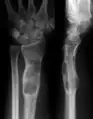

X-ray showing calcified enchondromas localized in finger a 37-year-old patient affected with Ollier disease

X-ray showing enchondromas localized in the lower part of the radius of a 37-year-old patient affected with Ollier disease